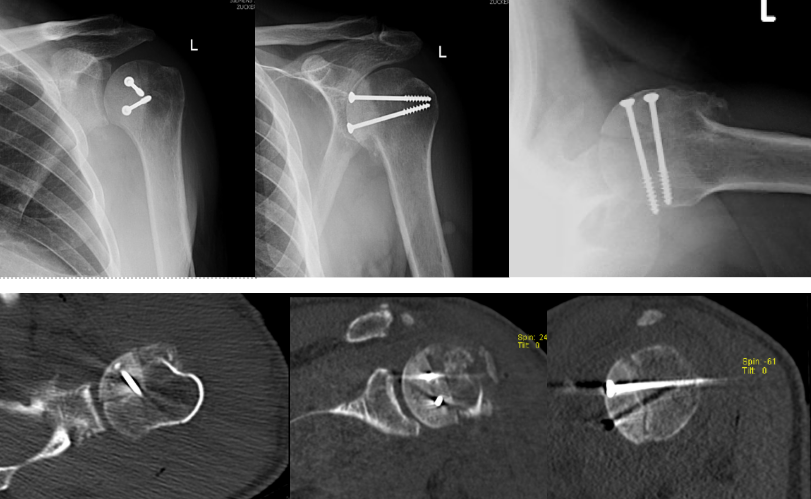

Standard imaging demonstrated a posterior dislocation of the glenohumeral joint with a large reverse Hill-Sachs defect engaged on the posterior glenoid rim (Figure 1). CT scan provided important information about the exact size of the defect, percentage involvement of the articular surface, and any associated damage to the glenoid. Measurements showed that 40 percent of the articular surface was involved.

The reverse Hill-Sachs defect involved approximately 40 percent of the articular surface, with nonviable cartilage at the base of the defect. The glenoid cartilage and remaining posterior humeral head cartilage were intact. A humeral head osteochondral allograft was contoured to match the wedge-shaped defect and provisionally stabilized with Kirschner wires. Definitive fixation was achieved with two countersunk 4.0-mm cancellous screws (20 mm and 45 mm) (Figures 2 and 3).